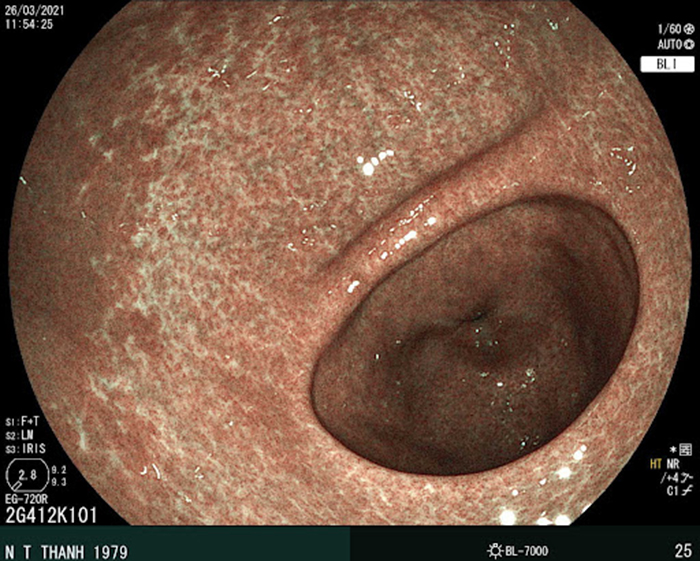

Biểu hiện của đau dạ dày mãn tính loại A là tình trạng viêm teo niêm mạc ở phần thân và phình vị dạ dày (Hình ảnh thực hiện tại MEDIPLUS)

Đây là bệnh phổ biến nhất trong các ca viêm dạ dày mạn tính. Biểu hiện chủ yếu tập trung ở hang vị và có thể lan rộng ra, gây tổn thương ở nhiều vùng trên dạ dày.